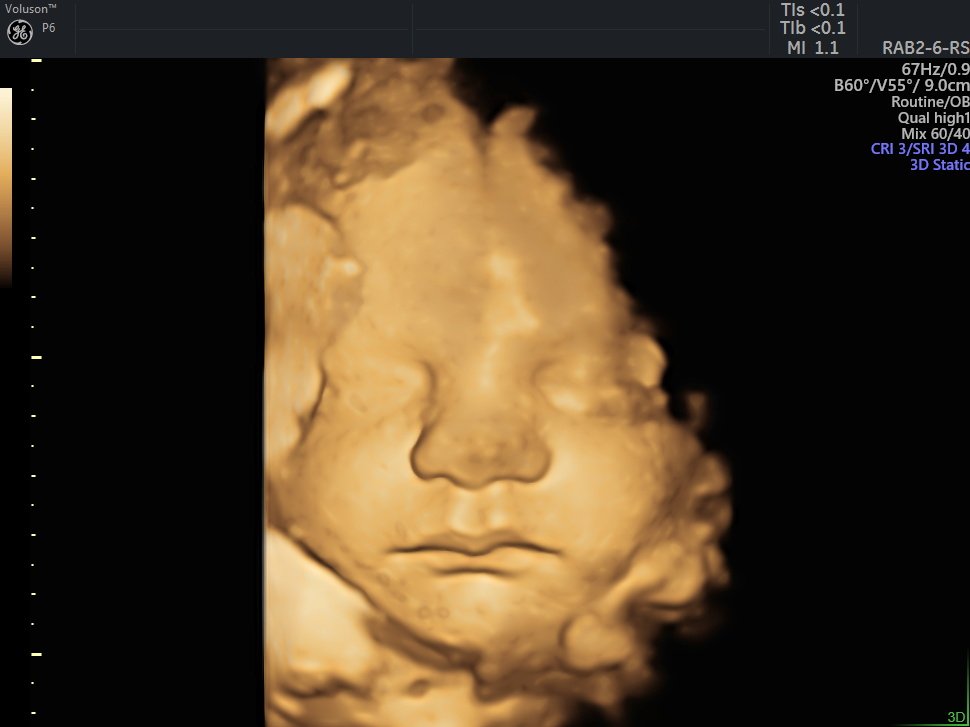

4 D Ultrasonografi

4 Boyutlu (Renkli) Ultrason ve Doppler Ultrasonografi